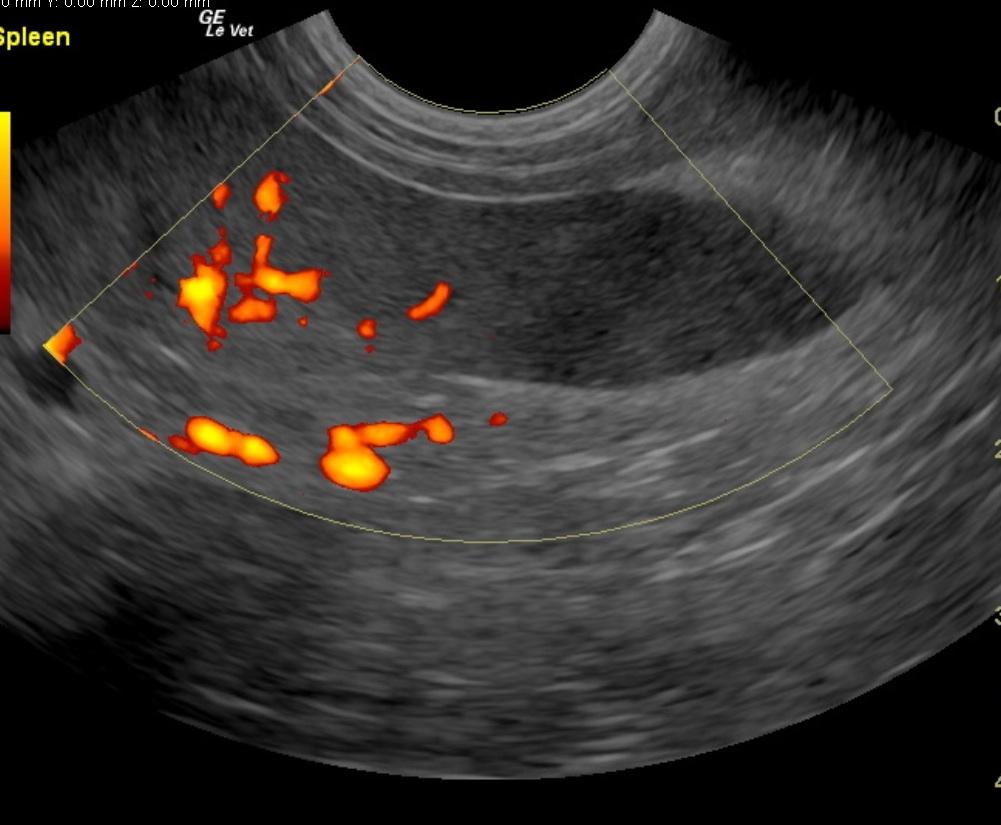

A 7-year-old FS Jack Russell Terrier with a history of regulated hypothyroidism, was presented for vomiting, lateral recumbency, and abdominal pain following ingestion of a ham bone. The owner also reported that the patient had been showing polyuria/polydipsia prior to the incident. On physical examination, the patient was laterally recumbent and very painful. CBC showed polycythemia and low band neutrophils. On blood chemistry, mildly elevated BUN, elevated creatinine, elevated ALP activity, elevated lipase, severely elevated ALT activity, and elevated cPLI were evident. A hemorrhagic diathesis was present on coagulation panel. Blood pressure was 145/80. The patient was treated with I.V. fluids, hetastarch, morphine/ketamine drip, fresh frozen plasma, antibiotics, and placed in an oxygen cage. On survey abdominal radiographs, bony fragments were evident in the gastrointestinal tract. The patient was sedated, given an enema, and a large piece of bone was produced. After 42 hours on therapy the patient developed dyspnea, which, on survey thoracic radiographs, was suggestive of fluid overload. Lasix was administered, which resulted in resolution of the dyspnea. Recheck blood chemistry showed hypoproteinemia, elevated ALP activity, hyperglycemia, improved azotemia, and normalization of cPLI. Physical examination, after 72 hours of supportive care, found the patient BAR and ambulatory, not interested in food, and still extremely painful upon palpation of the right mid-abdomen. Syringe feedings were started, which were well tolerated with no vomiting. However, the following morning the patient was less bright and more painful in the abdomen.